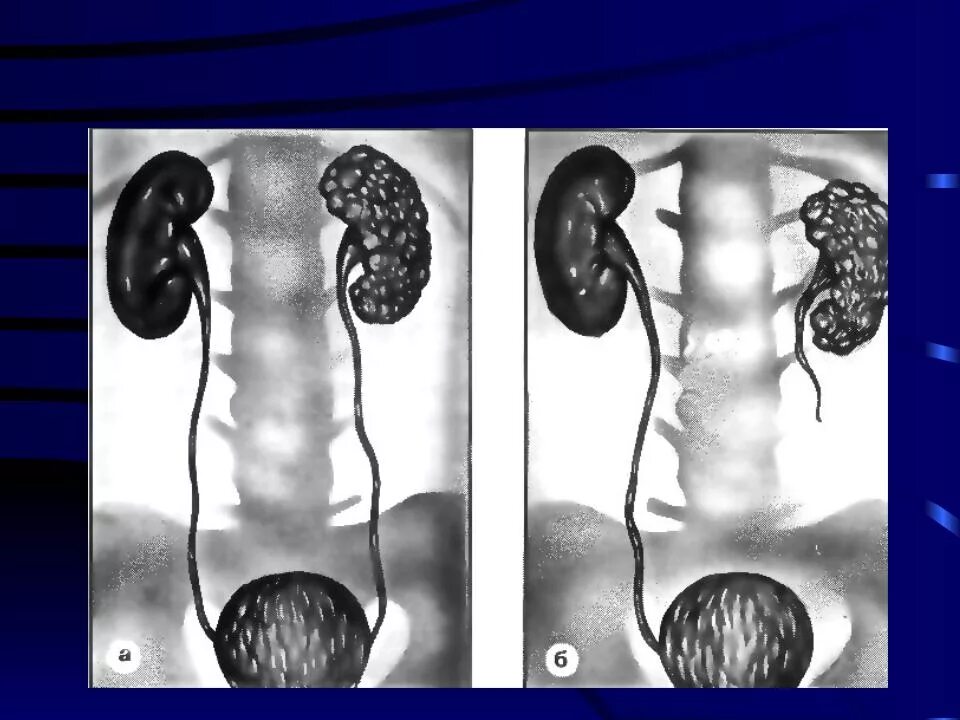

Мультикистозная почек плода